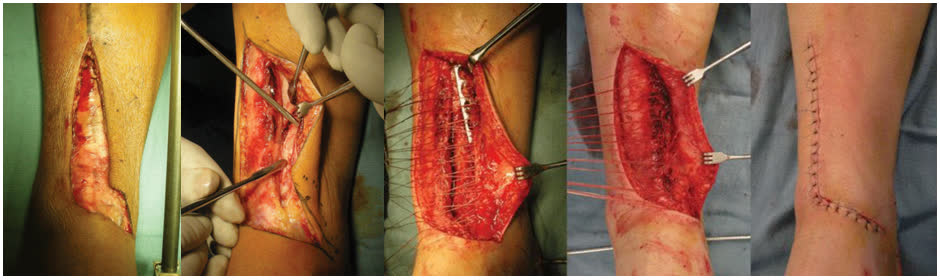

Принципы фиксации

Фрагмент-специфическая фиксация по колоннам

Принцип колонного остеосинтеза: каждая повреждённая колонна фиксируется индивидуально через оптимальный для неё доступ. При переломах типа С необходима стабилизация минимум двух колонн (для четырёхколонной теории); фиксация всех повреждённых колонн не всегда обязательна — стабилизация 2–3 ключевых колонн может быть достаточной [Bakan et al., Injury, 2023].

Медиальная колонна — ключевая для механической стабильности. Варианты фиксации: опорная (buttress) пластина по медиальной поверхности, одна треть трубчатая пластина или винты. Одна треть трубчатая пластина обеспечивает более раннюю осевую нагрузку и меньшую потерю репозиции по сравнению с изолированными винтами [Wang et al., Ann Transl Med, 2022]. Стабилизация медиальной колонны + как минимум одной дополнительной колонны — минимальный объём при сложных переломах [Bastias & Lagos, 2020].

Передняя колонна (переднелатеральная) — фиксация дистальной Т-образной или L-образной опорной пластиной. Пластина устанавливается как buttress по передней поверхности, предотвращая вторичное смещение переднего фрагмента (Chaput/Tillaux-Chaput). Переднелатеральный фрагмент присутствует при большинстве переломов пилона с вовлечением суставной поверхности [Rammelt et al., JBJS Am, 2022].

Средняя (центральная) колонна — зона импакции суставной поверхности (die-punch). Фиксация через заднемедиальный доступ. Техника: подъём импактированного суставного фрагмента, заполнение дефекта аутокостью или костным заменителем, фиксация субхондральными винтами и/или опорной пластиной. Ступенька суставной поверхности ≥2 мм достоверно ухудшает исходы [Gao et al., 2023].

Заднелатеральная колонна (задняя лодыжка / фрагмент Volkmann) — задняя антискользящая (antiglide) пластина через заднелатеральный доступ. Одномоментная фиксация с малоберцовой костью через тот же доступ экономит время и снижает хирургическую агрессию. Задняя колонна повреждается в 88% случаев — это наиболее часто вовлекаемая колонна [Lou et al., Injury, 2023].

Латеральная колонна (малоберцовая кость) — опорная или мостовидная пластина. Показания к фиксации: использование малоберцовой кости как инструмента непрямой репозиции, повреждение синдесмоза, латеральная нестабильность.

Импакция суставной поверхности

Центральная импакция (die-punch) — один из ключевых элементов, определяющих исход. Техника восстановления: через задний или передний доступ импактированный фрагмент поднимается до уровня окружающей суставной поверхности. Образовавшийся метафизарный дефект заполняется аутокостью (из гребня подвздошной кости, проксимального отдела большеберцовой кости) или синтетическим костным заменителем (трикальцийфосфат, гидроксиапатит). Субхондральные винты или пластина создают опору снизу, предотвращая вторичное проседание.

Качество репозиции суставной поверхности — главный модифицируемый фактор исхода. Цель — анатомичная репозиция с остаточной ступенькой <2 мм.

MIPO vs стандартный ORIF

Систематический обзор (Sourougeon et al., Foot Ankle Surg, 2023, N=673): отличные и хорошие результаты в 87,3% случаев, глубокая инфекция 0,15%, несращение 0,59%, общая частота осложнений 35%.

Первое РКИ MIPO vs ORIF (Erivan et al., OTSR, 2025, N=54): MIPO не продемонстрировал превосходства над стандартным ORIF через 12 месяцев. Идентичная частота инфекции (15,4% в обеих группах). ORIF показал лучшие функциональные результаты через 3 месяца (AOFAS, FADI, MAZUR), но к 6 месяцам различия нивелировались.